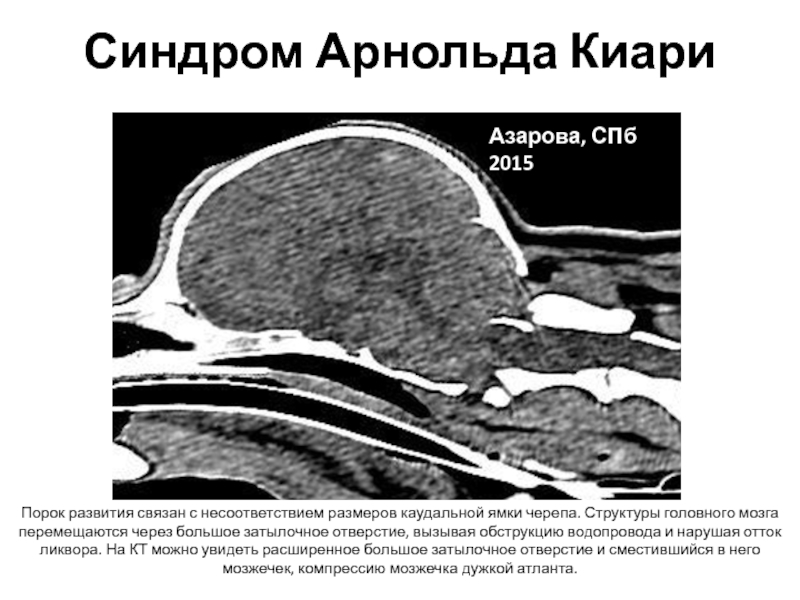

Компьютерная томография в неврологии презентация - 86 фото